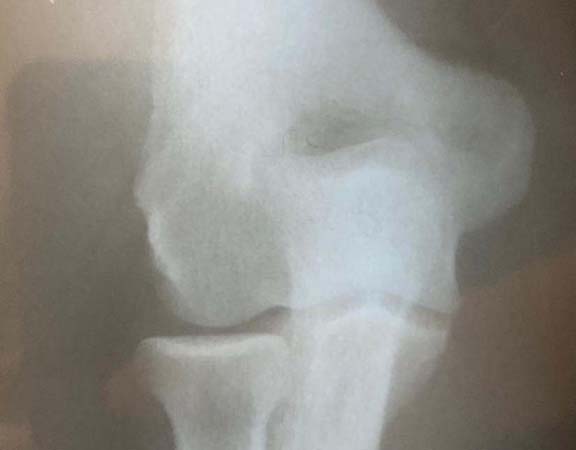

Fraturas do cotovelo

O cotovelo é composto por três ossos: o úmero, ulna e o rádio. As Fraturas do Cotovelo podem acontecer nesses três locais, isoladamente ou em conjunto, acompanhadas ou não por alguma lesão ligamentar ou de nervo. Assim como todas as fraturas, as de cotovelo se dão quando há um rompimento em um ou mais locais do osso. As que ocorrem nessa articulação são: a fratura da cabeça do rádio, a mais comum entre todas; fratura da porção distal do úmero e do olécrano (parte de trás do cotovelo, parte da ulna). As fraturas podem ocorrer em decorrência de uma queda com o braço estendido ou por traumas de alto impacto, como os acidentes automobilísticos. Dor, edema, hematoma e deformidade são os principais sintomas da doença. O diagnóstico e feito através da realização de radiografia e pela tomografia computadorizada. O tratamento pode ser realizado com imobilização gessada para aquelas fraturas bem alinhadas e o tratamento cirúrgico para as fraturas desalinhadas.